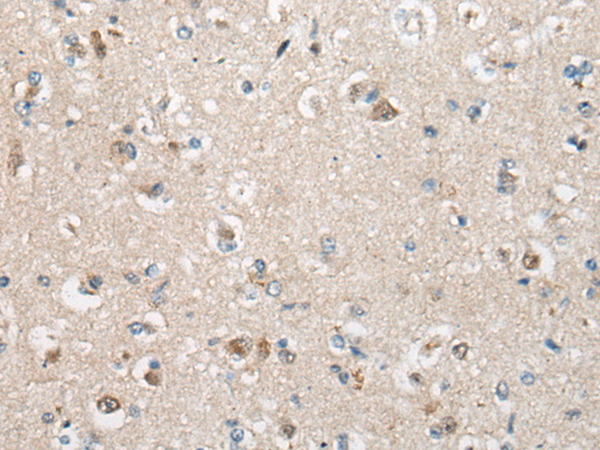

IHC positive control: |

Human brain |